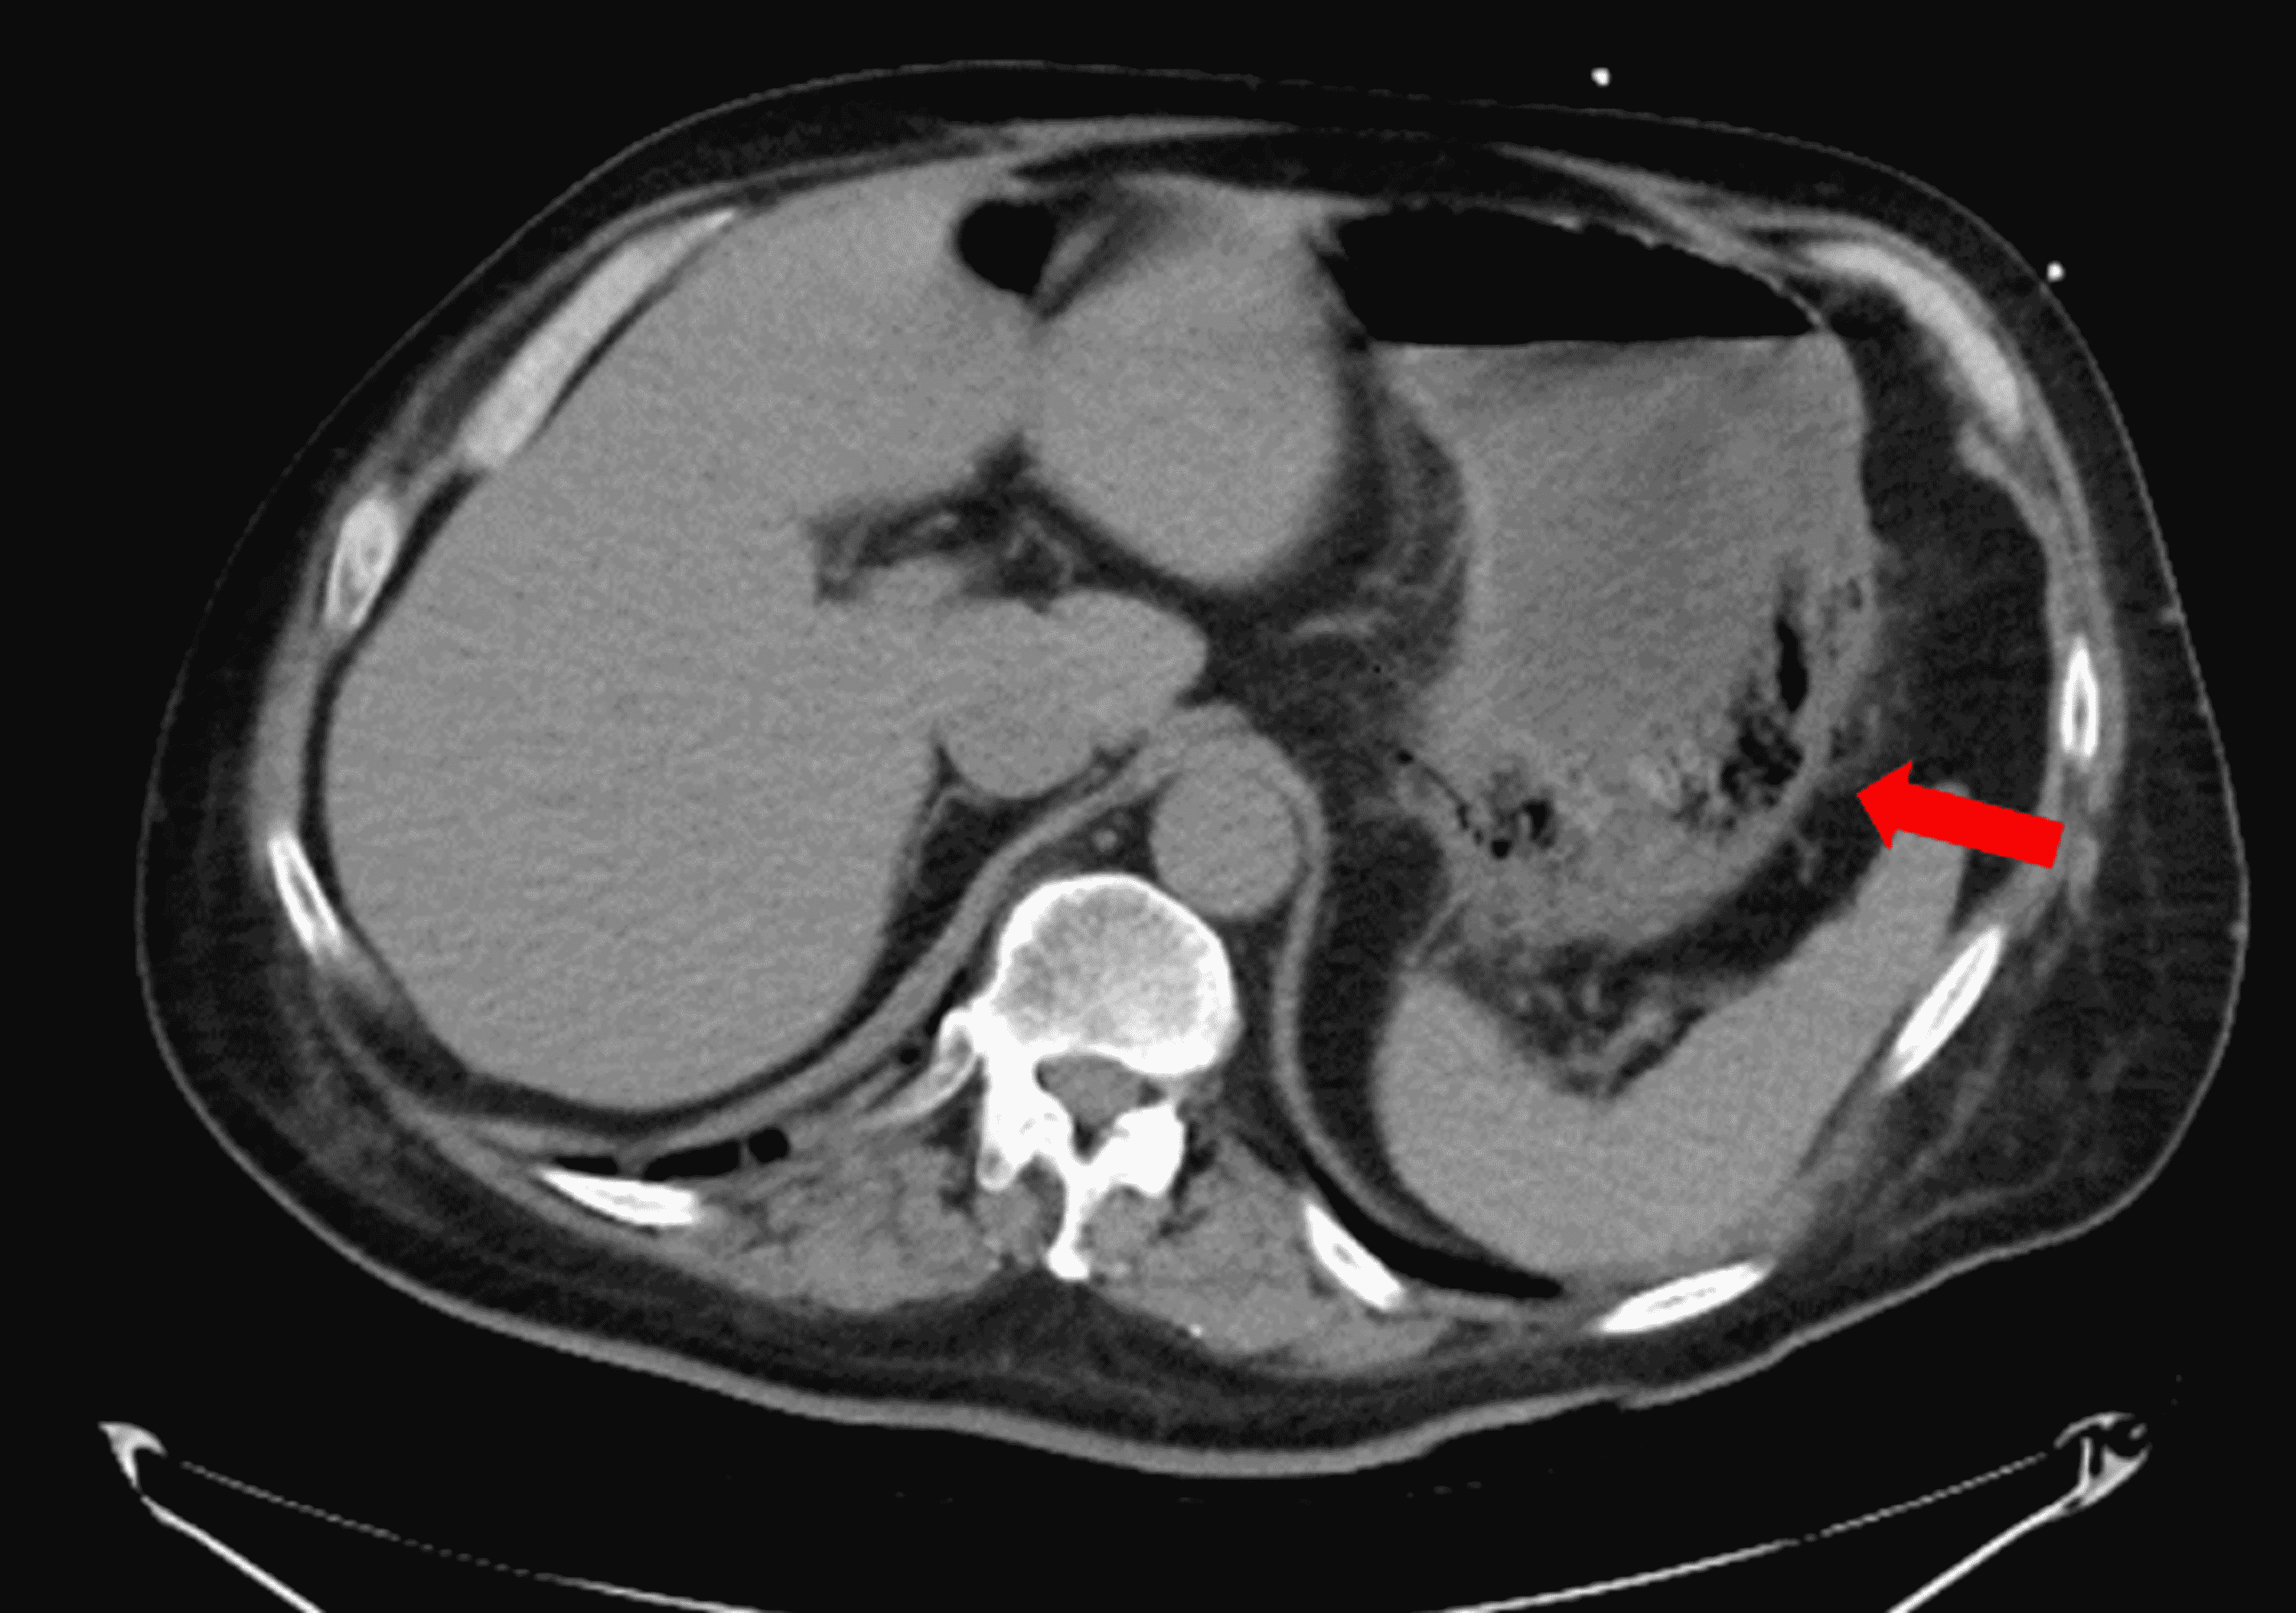

Case Report Of Emphysematous Gastritis . Emphysematous gastritis (eg) is an exceedingly rare cause of severe abdominal pain with an associated mortality reported at greater. 1 as in our case, diabetes mellitus, malnutrition, and renal failure. Emphysematous gastritis (eg) is a rare condition characterized by air within the. Recent case literature shows a trend towards conservative management for emphysematous gastritis with several. Our case was notable in that appropriate and prompt conservative treatments prevented fatal outcome and led to disappearance of hepatic portal venous gas, and this was the.

Recent case literature shows a trend towards conservative management for emphysematous gastritis with several. Emphysematous gastritis (eg) is an exceedingly rare cause of severe abdominal pain with an associated mortality reported at greater. Emphysematous gastritis (eg) is a rare condition characterized by air within the. 1 as in our case, diabetes mellitus, malnutrition, and renal failure. Our case was notable in that appropriate and prompt conservative treatments prevented fatal outcome and led to disappearance of hepatic portal venous gas, and this was the.

Case Report Of Emphysematous Gastritis Emphysematous gastritis (eg) is an exceedingly rare cause of severe abdominal pain with an associated mortality reported at greater. Recent case literature shows a trend towards conservative management for emphysematous gastritis with several. Our case was notable in that appropriate and prompt conservative treatments prevented fatal outcome and led to disappearance of hepatic portal venous gas, and this was the. 1 as in our case, diabetes mellitus, malnutrition, and renal failure. Emphysematous gastritis (eg) is an exceedingly rare cause of severe abdominal pain with an associated mortality reported at greater. Emphysematous gastritis (eg) is a rare condition characterized by air within the.